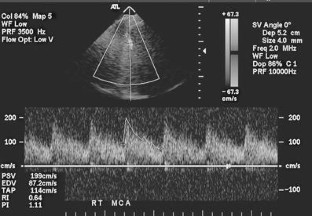

Fig. 2